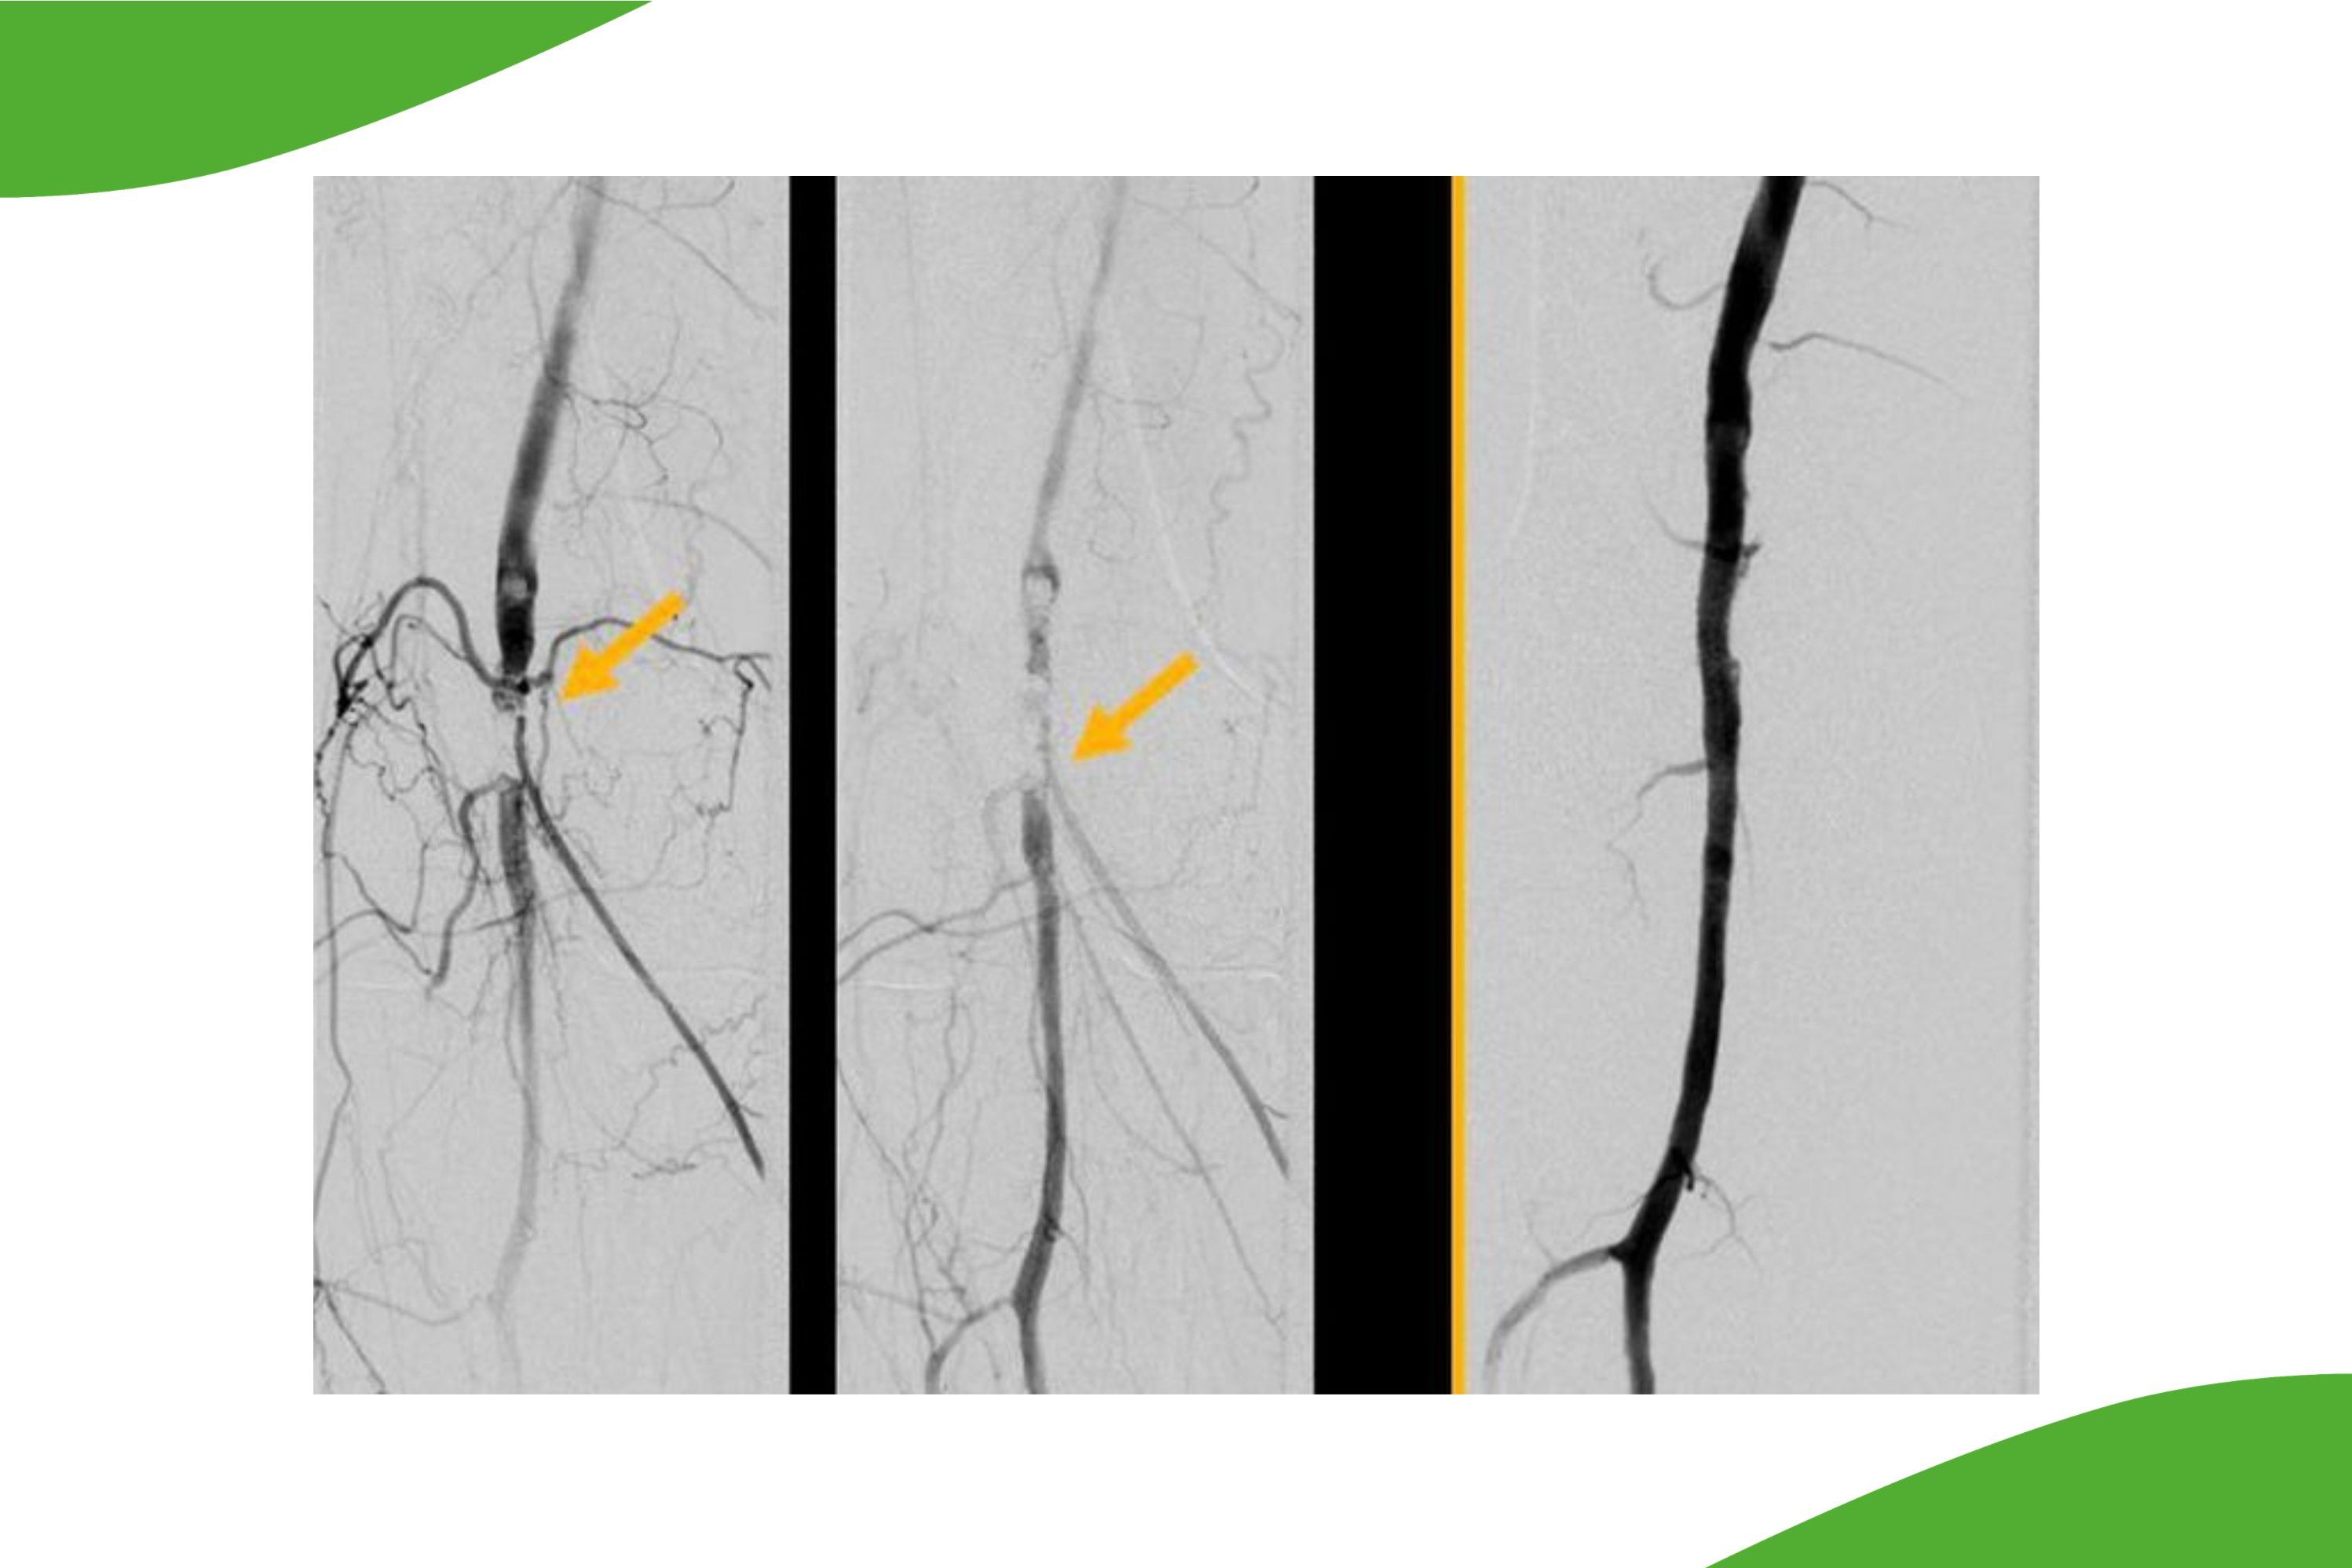

Eine spezielle Expertise besteht in der Durchführung von ggf. erforderlichen weiteren Behandlungen nach Aortenstentgraft (EVAR bzw. FEVAR). In seltenen Fällen können Undichtigkeiten entstehen oder über kleine Seitenäste kann auch eine Restdurchblutung des Aneurysmasackes entstehen (sogenannte Endoleaks), welche dann zum Teil behandelt werden müssen. Durch die Verfügbarkeit verschiedenster Materialien auch von kleinsten Kathetern, welche ansonsten im Bereich der Neuroradiologie und für Interventionen im Gehirn oder im Rückemarksbereich eingesetzt werden, kann nun auch über kleinste Kollateralen der Zufluss aufgesucht werden und entweder mit Coils oder Plugs behandelt werden oder aber auch Zuflüsse und der Aneurysmasack selber mit speziellen Embolisaten ausgekleidet werden (siehe Abbildung).

EVAR Repair (links) bei sog. Endoleak u.a. über Lumbalgefässe (Pfeilspitzen) und großer Kontrastmittelansammlung im Aneurysmasack (orange Pfeile links) mit deutlichem Größenwachstum des Aneurysmasackes trotz Endograft (extern vor mehreren Jahren). Onyx-Injektion (Mitte) mit Mikrokatheter am Aneurysmasack (weißer Pfeil), Okklusion des Endoleaks und beider Lumbagefässmündugnen mit dem Onyx-Cast über eine Mikrokatheterposition. In der CT Kontrolle ist das Embolisat in den ehemaligen Zuflüssen gut erkennbar.